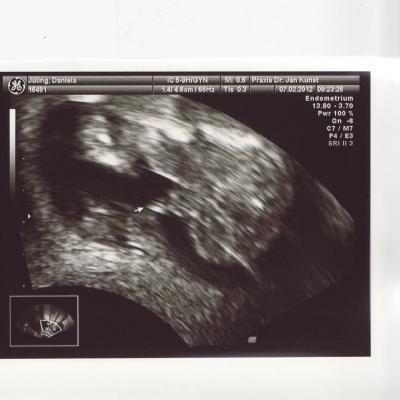

Vielen lieben Dank an alle die an mich gedacht haben und feste Daumen gedrückt haben. Bin gerade zurückgekommen und es ist alles in Ordnung. Ich bin heute 15+3 und er konnte mir auch schon sagen das es ein Junge wird. Bin total sprachlos. Nur leider konnte er nicht genau messen wie gross der kleine Racker schon ist da er ordentlich geturnt hat während der Untersuchung. Mir ist auf jeden Fall ein riesengrosser Fels vom Herz gefallen und ich bin total überwältigt.

Bild zu Zurück vom FA... - Forum für August - Mamis